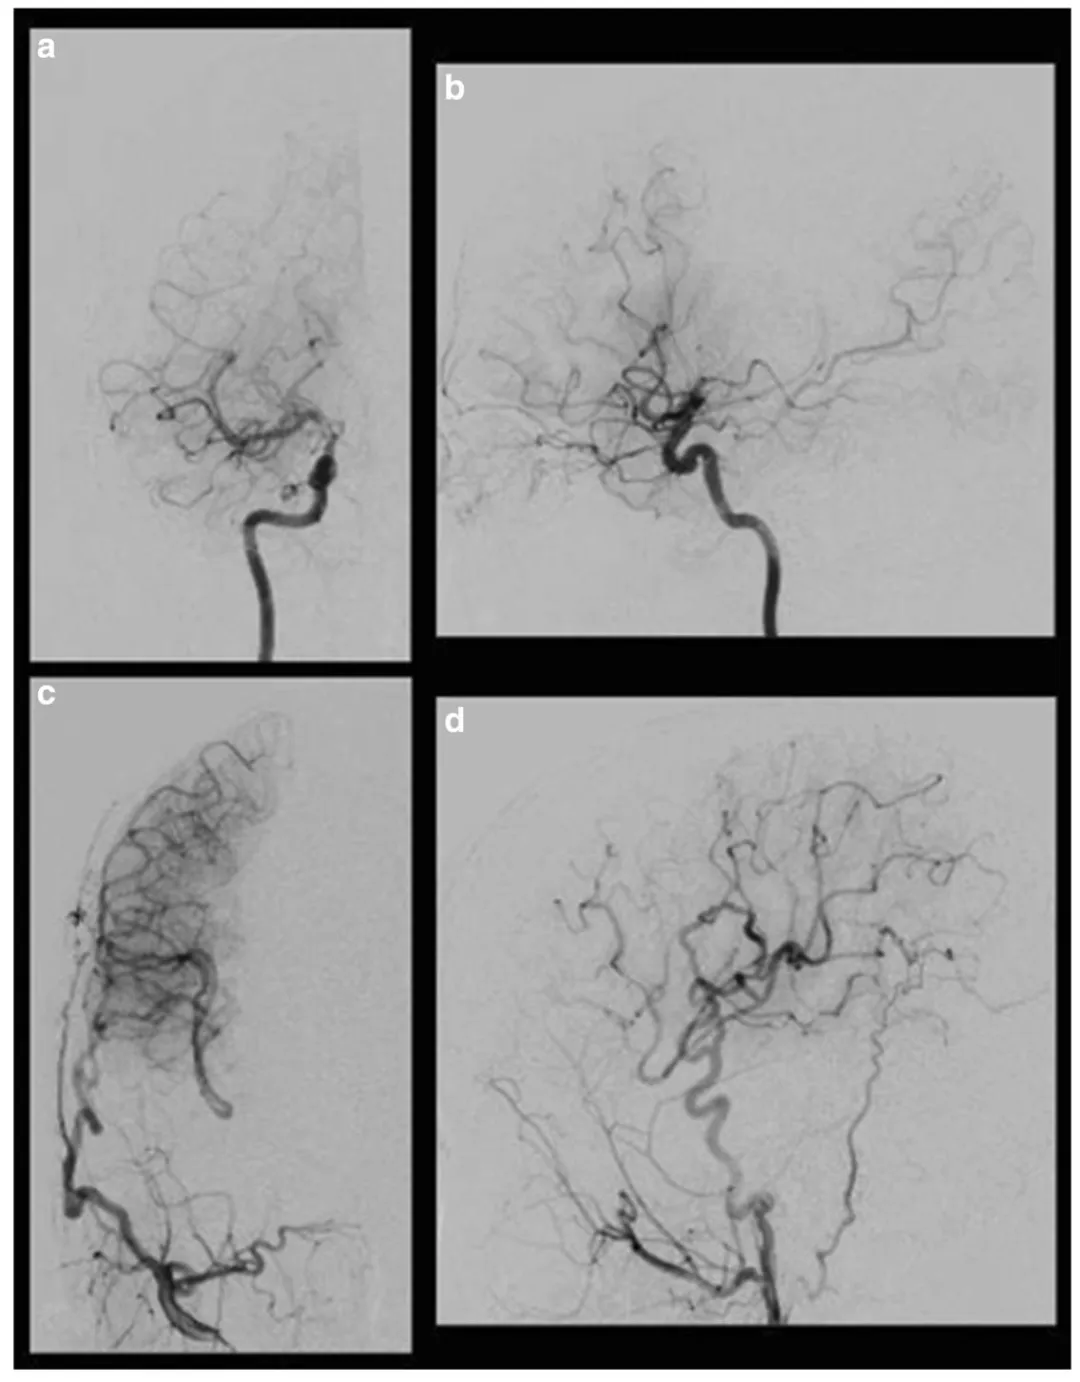

术后7个月的复查结果更是给了医生们一颗定心丸:血管造影清晰显示(图3),新搭建的血管通畅良好,颈外动脉的血流通过搭桥血管,源源不断地供应到右侧大脑中动脉区域。这意味着手术不仅解决了症状,更从根本上改善了脑组织的血液灌注。

图三,术后右侧颈动脉血管造影显示,通过右侧颈外动脉的搭桥血管向大脑中动脉(MCA)和大脑前动脉(ACA)供血不足区域供血。右侧颈内动脉正位观(a)和侧位观(b);右侧颈外动脉正位观(c)和侧位观(d)